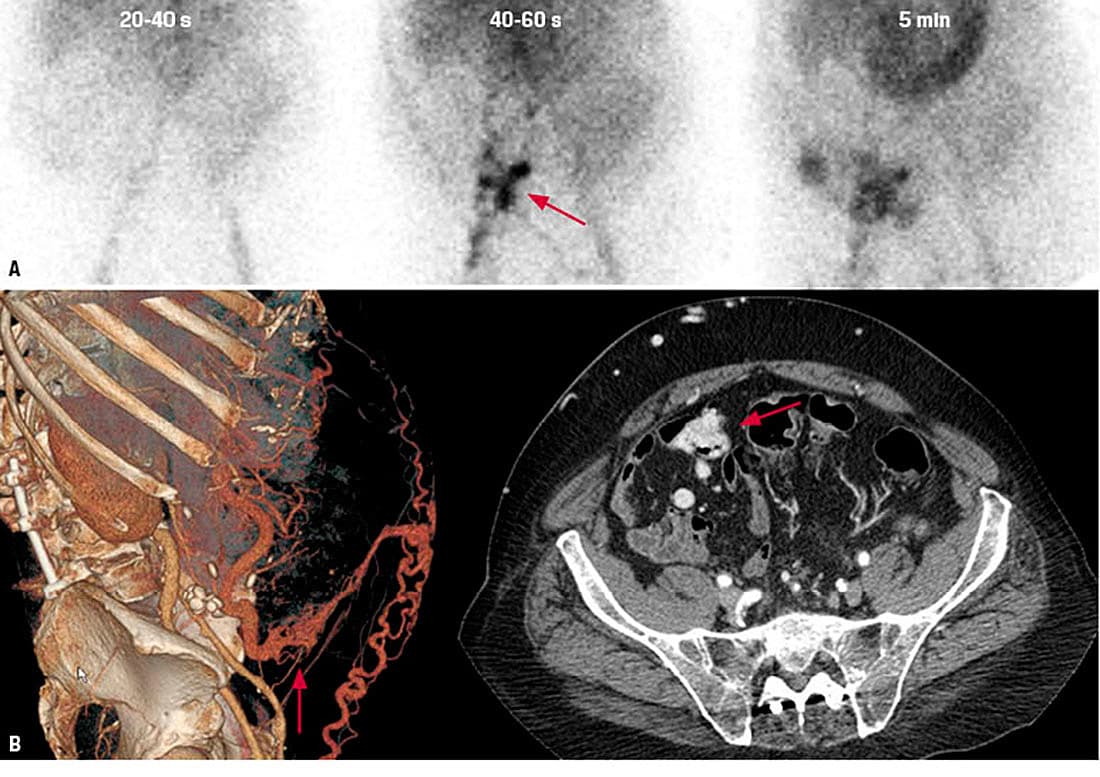

B-hæmoglobinniveauet var faldende trods gentagne blodtransfusioner. Ved gastroskopi, koloskopi og CT-angiografi fandt man ikke blødningskilden. En blødningsscintigrafi afslørede blødning i nedre, højre abdomen (A, rød pil). En gennemgang af CT-angiografien viste svært dilaterede vener i tæt relation til terminale ileum i forbindelse med dilaterede umbilikale og mesenterielle kar (B, røde pile). Ved eksplorativ laparoskopi med tyndtarmsresektion ca. 40 cm fra ileocækalstedet fandtes tarmen adhærent til forreste bugvæg og omgivet af varikøse vener. B-hæmoglobinniveauet var efterfølgende stabilt. En mikroskopisk undersøgelse af tyndtarmsresektatet viste store dilaterede kar i submucosa og krøs, hvilket er foreneligt med varicer.

Hos patienter med portal hypertension kan adhærenser mellem tarm og abdominalvæg medføre portokavale anastomoser og mesenterielle varicer [1]. Selvom tilstanden er en sjælden årsag til hæmatokesi, bør den overvejes differentialdiagnostisk, især hos patienter, som har levercirrose og tidligere har fået foretaget abdominalkirurgi [2]. Blødningsscintigrafi er et godt diagnostisk supplement til udredning af patienter med akut gastrointestinal blødning [3].